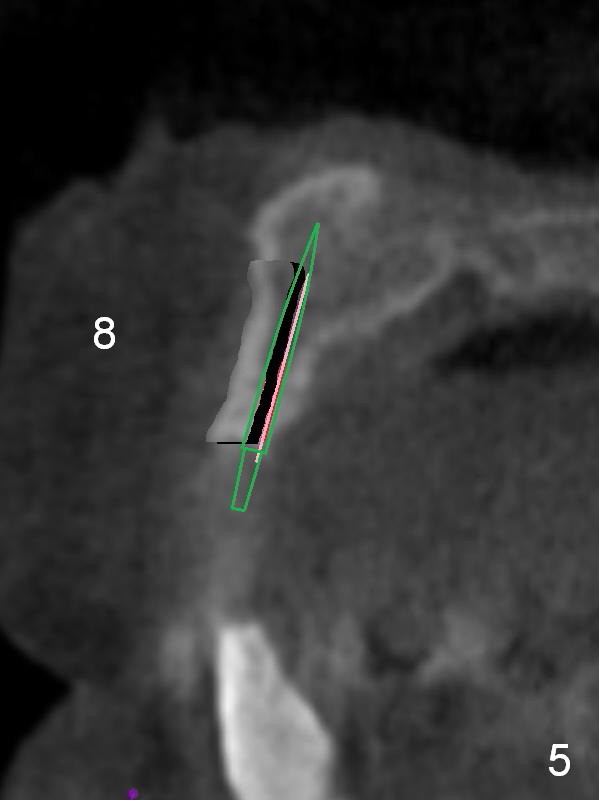

After implant reconstruction of the lower right and left (including #19) regions, the same treatment is considered in the atrophic anterior maxilla (#8-13) for anchorage for upper left molar cross bite correction. The smallest implants are to be placed in the each of the sites with different strategies. For example, at the site of #8 (Fig,1,2), ridge split with wheel (Fig.3) and microsteotomes (Fig.4) are used to place 1-piece implant (3x14 mm). The site of #9 has a pointed ridge and a wide base (Fig.6); a 1-piece angled implant (3x14 mm 15 °) is placed palatally (Fig.7). The ridge and base at #10 are narrow (Fig.8); after truncating the pointed ridge, a 2.0 or 2.5 mm 1-piece implant is placed parallel to the palatal wall (Fig.9).